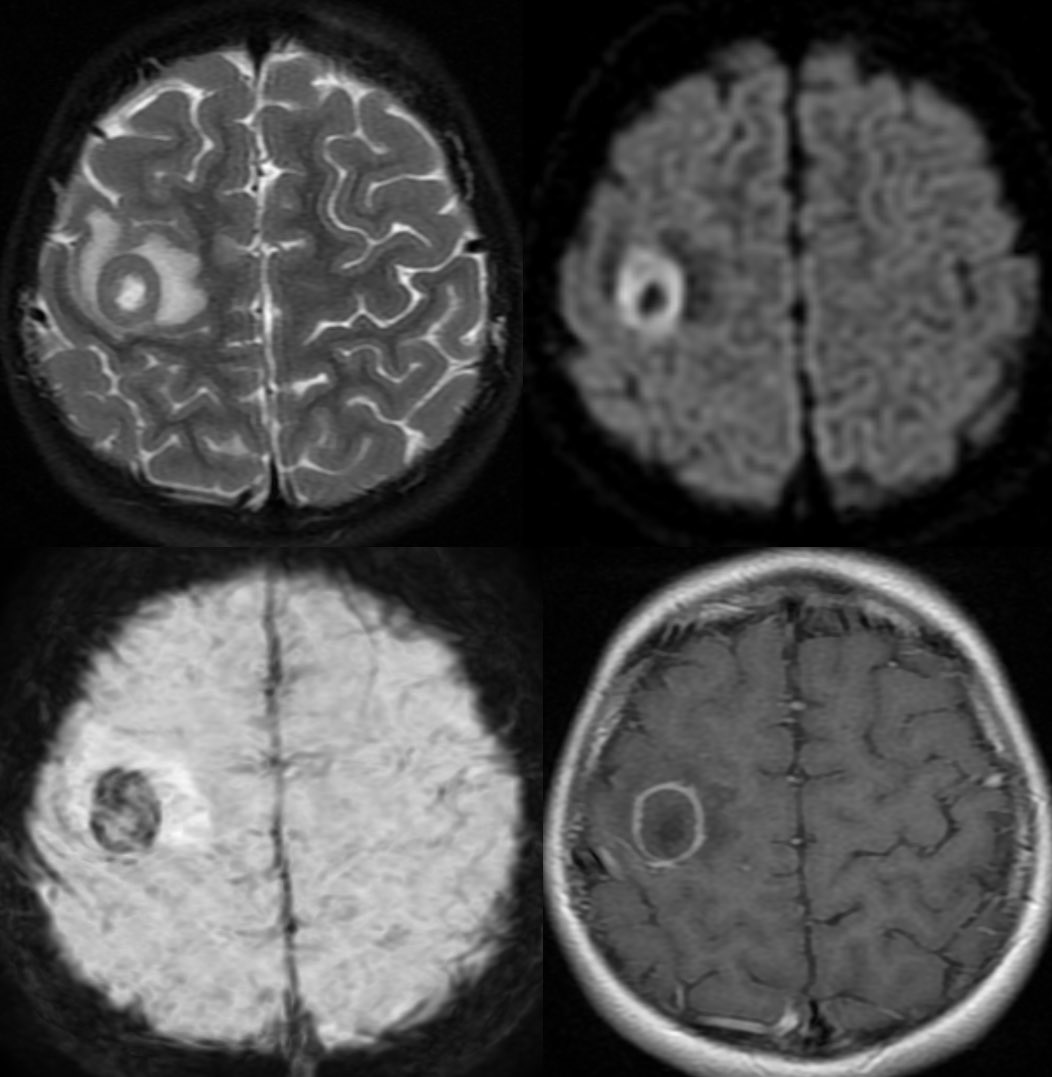

Interesting case of complicated acute bacterial rhinosinusitis in this child with no PMH presenting w/ HA, fever & L sided weakness

MR shows abnormal signal filling the sinuses with associated restricted diffusion 2/2 purulent material

Post contrast we see areas of relative hypoenhancement in comparison to the normal mucosa on the contralateral side ImageImageImage

There is smooth pachymeningeal enhancement, suggestive of intracranial extension as well as an abscess in the right frontal lobe ImageImage